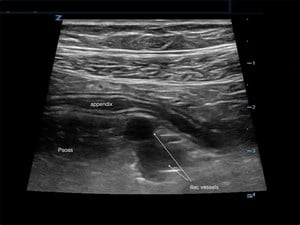

Sound Waves & Sirens: Creating a SonOlympics for EMS Teams Without Prior Ultrasound Training

As a new and enthusiastic member of the ACEP Prehospital, Austere, and Tactical Ultrasound Subcommittee, I’m thrilled to contribute to our mission of expanding the use of ultrasound in prehospital a...